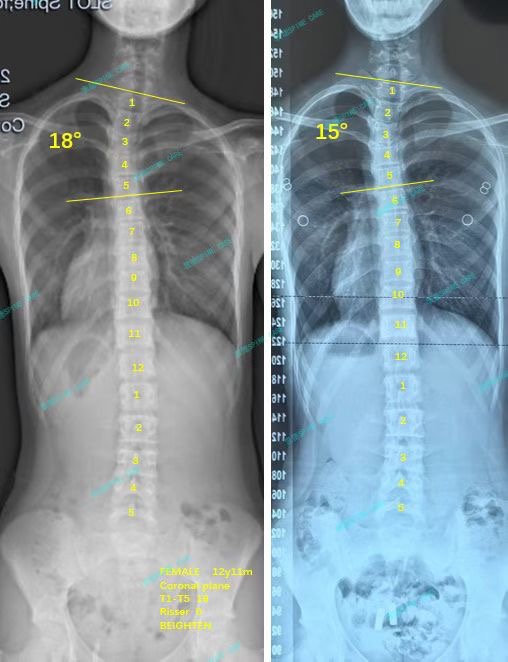

衷德脊柱,我们只关注侧弯保守治疗~

Zhongde Spine, bending no breaking ~